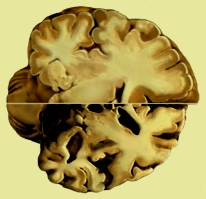

Organo pensante

Por lo menos el cerebro esta tomando conciencia real de sí mismo, ahora sabe que si él como órgano muere, todo lo demás del cuerpo es inservible, inútil. Sabe ahora que si pudiera ser transplantado en otro cuerpo, seguiría viviendo con sus aciertos y errores propios de sí, no del cuerpo que lo alojaría.